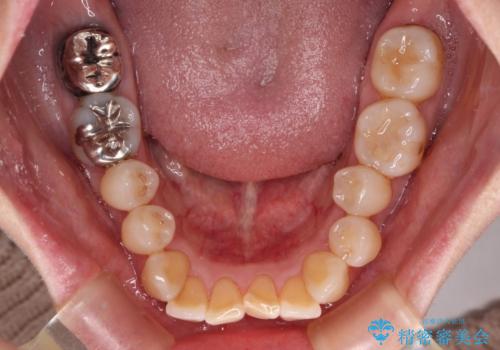

- 口元の突出感を気にして来院された患者様です。

上下前歯が著しく前突している状態であったので、上下左右の小臼歯4本を抜歯し、ワイヤー装置にて矯正治療を行うこととしました。

上顎左側は第二小臼歯に大きなむし歯があったため、通常は第一小臼歯を抜歯するところ、イレギュラーに第二小臼歯を抜歯することとしました。

抜歯する第二小臼歯の後方の歯は神経近くにまで及ぶむし歯があったため、事前に処置をしておき、矯正治療後にオールセラミッククラウンにて補綴治療を行うこととしました。